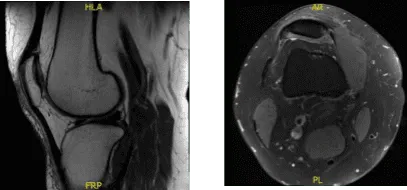

Se realizaron radiografías y resonancias magnéticas en la consulta. Se encontró desgarro vertical en el borde libre del menisco medial del cuerno posterior, con un leve deshilachamiento en la parte inferior inferior/borde libre del segmento corporal. Pérdida condral leve del compartimento femorotibial medial. Desgaste condral leve del compartimento patelofemoral, preferentemente sobre la parte medial del compartimento.

Inclinación lateral de la rótula con posición lateral leve de la rótula. Estos hallazgos pueden observarse en el contexto del trasvase de malta rotuliana. Características que pueden observarse en el contexto del síndrome de fricción de la banda iliotibial.